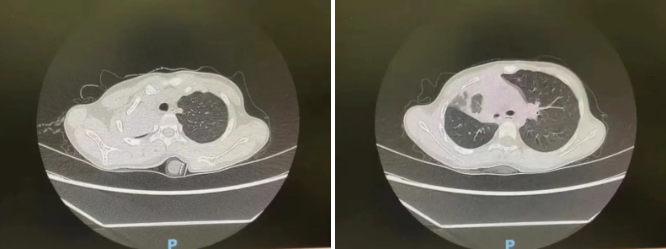

病情就是命令,呼吸科应急团队牟向东、主治医师李理、护士白凤辉同时紧急赶往医院,手术室团队也迅速做好了准备。术中,麻醉科副主任高志峰经过评估,采用气管插管迅速建立全身麻醉下机械通气,期间患儿血氧饱和度及双肺呼吸音明显下降,气道压力在41-42mmHg之间,明显升高。

牟向东立即行气管镜检查,发现患儿左右主支气管全部被脓性分泌物阻塞,粘稠的痰液堵住了患儿的气道,伴气道黏膜肿胀,大量的脓性分泌物还从远端支气管不断涌出,导致血氧下降不能维持正常。经过反复支气管镜吸痰并多次支气管肺泡灌洗后,痰液明显减少,同时听诊肺部弥漫性哮鸣音,血氧不稳,即刻静脉及经支气管镜局部给予地塞米松治疗。